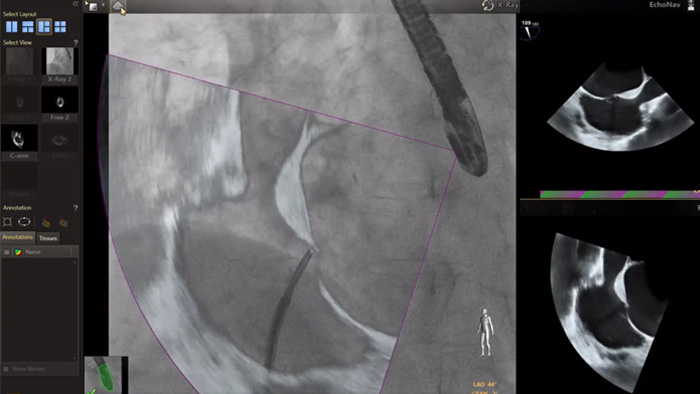

En el centro de nuestra suite, la exclusiva solución EchoNavigator es el ejemplo emblemático del compromiso de Philips con la multimodalidad y la integración del flujo de trabajo, aporta lo mejor de ambos mundos del líder de la industria en soluciones cardíacas intervencionistas de rayos X y ecografía.

Implementación de la superposición de la ETE 3D en vivo de la oclusión de la LAA con EchoNavigator

Guía de punción transeptal mediante EchoNavigator